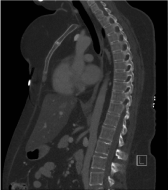

Figure 6. Sagittal CT image of chest and abdomen demonstrating the normal vertebral height and alignment of vertebral spine with no evidence of osteoporotic fractures

A subsequent contrast enhanced computer tomogram (Figure 2, 3, 6) of the thorax, abdomen and pelvis revealed multiple sclerotic ribs with periosteal bone formation. No destructive bony lesion or fractures were found elsewhere within the visualised skeleton (Figure 4) and pituitary gland appeared normal (Figure 5).